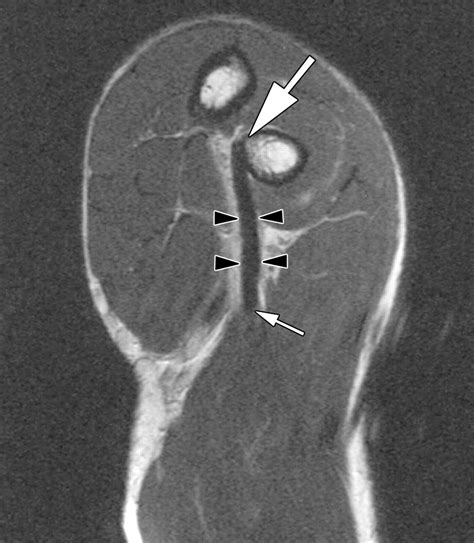

• Imaging Tests: X-rays, ultrasound, and MRI scans can provide detailed images of the elbow and forearm, helping to confirm the diagnosis and assess the extent of the injury.